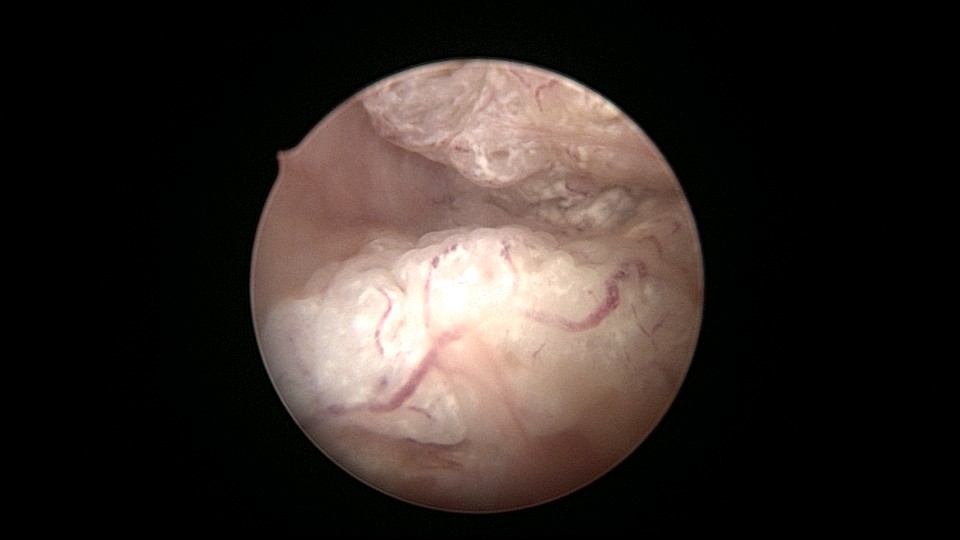

患者55岁,G4P1,顺产1次。安环16年,绝经5年,外院取环失败。子宫前位,宫颈萎缩,宫腔下段左后壁见假道,假道内见肌瘤结节突出,爱母环位置正常,宫腔左侧壁及前壁见占位质脆组织,表面有异常粗大血管。异物钳顺利取出节育环,占位组织病检为内膜样癌。取环造成的假道让病人因祸得福,提前发现了子宫内膜样癌,得以及时手术治疗。